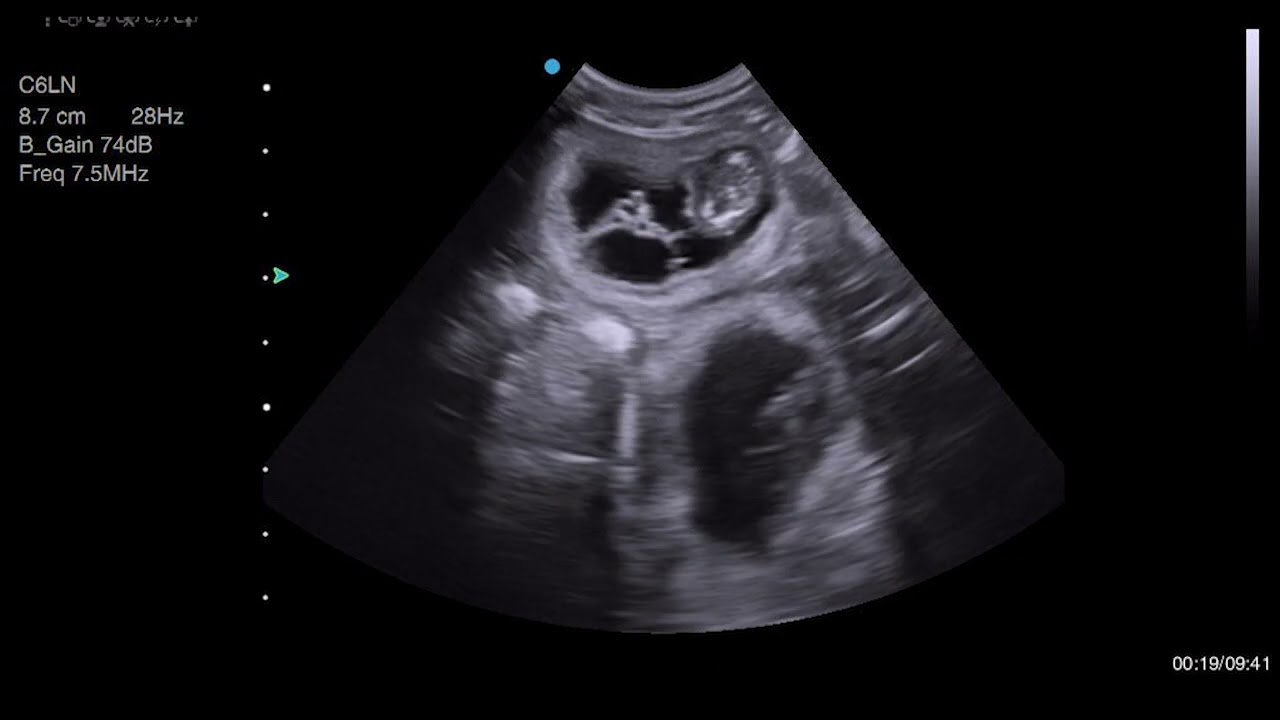

Two Feline Pregnancy Scans

Описание: Two cats came for their pregnancy scans today, both at similar stages of gestation. We used the ScanPad and Apogee 2300 to confirm pregnancy.